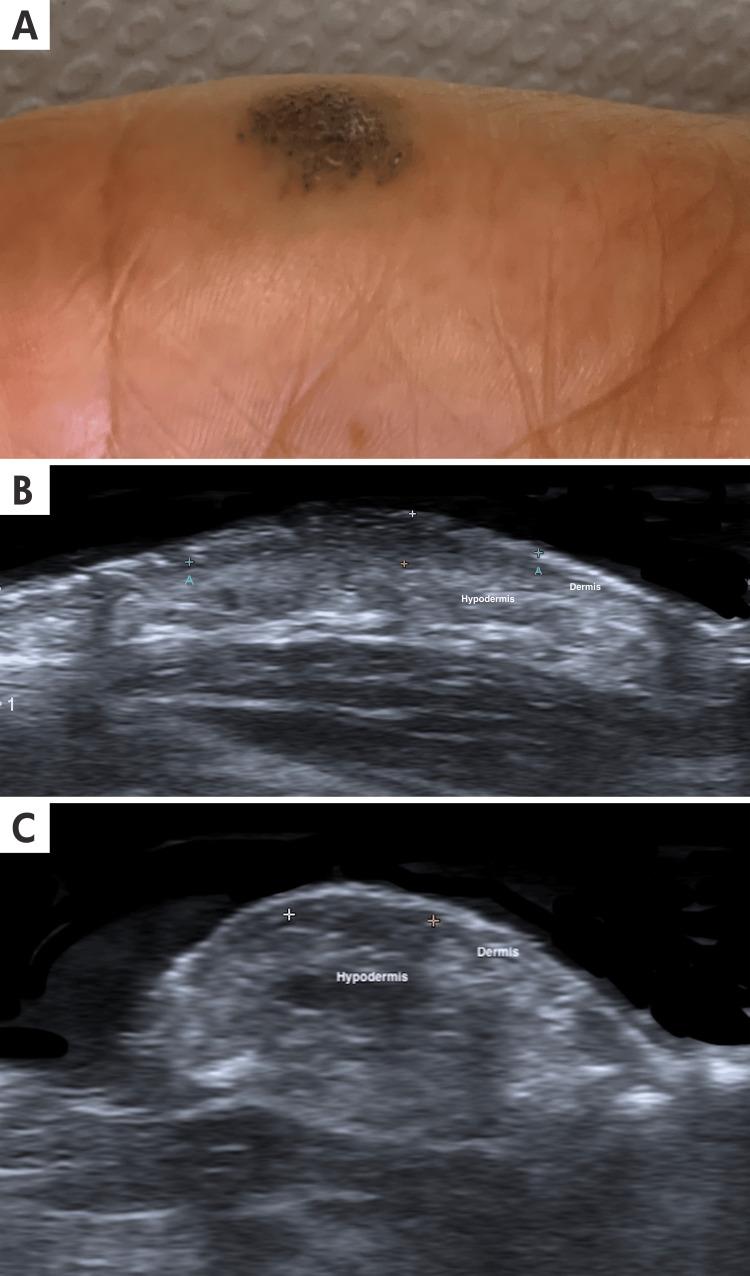

血管异常(VA)分为血管肿瘤或血管畸形。血管肿瘤以内皮细胞的肿瘤性增殖为特征,而血管畸形则是由于胚胎发育过程中调节血管通道发育的途径存在缺陷所致。皮肤超声已成为一种关键的诊断工具,通过提供详细的成像特征来区分VA与其他病症,并区分各种类型的VA。在本研究中,我们展示了通过皮肤超声识别和表征的少见VA病例,以说明这种检查方法在临床实践中的实用性。患者从临床记录(2021年2月至2024年2月)中随机选取,这些患者经组织学证实患有皮肤VA,年龄跨度为10至72岁。纳入标准要求有完整的临床记录和超声报告。该样本代表了六种不同的VA,并展示了临床实践中观察到的一系列并发症。所选病例包括五种血管肿瘤:化脓性肉芽肿、皮肤血管肉瘤、指外血管球瘤、樱桃状血管瘤和血管角皮瘤,以及一种血管畸形:疣状静脉畸形。尽管它们的临床表现各异,但皮肤超声对每种异常类型都显示出独特的特征,证明是皮肤VA多学科管理中的一种有价值的工具。这种成像方式能够进行精确评估并指导有效的治疗策略。

Solitary plantar hyperkeratotic plaque in a young male.

一名年轻男性足底出现孤立性角化过度斑块。